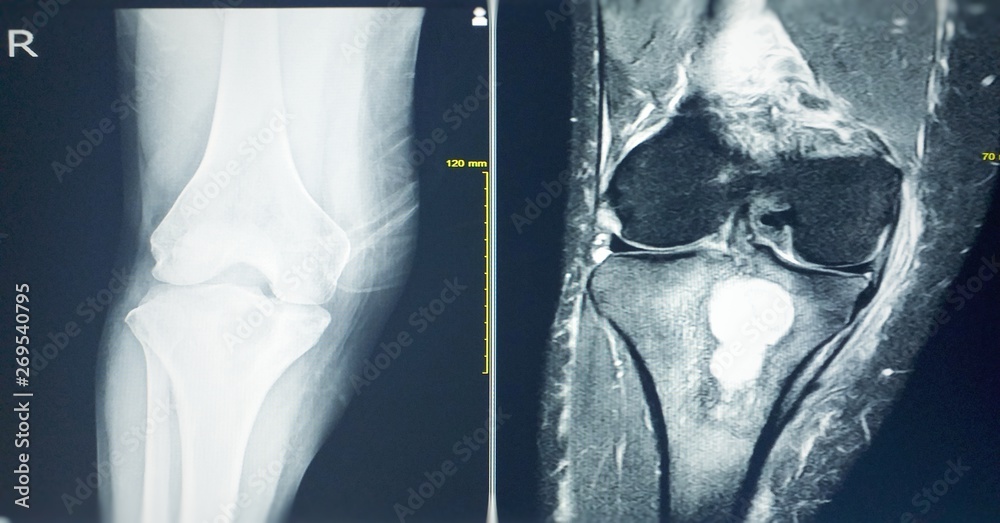

Knee Arthritis, MRI Stock Image C027/1211 Science Photo Library

MRI OF THE RIGHT KNEE History Right knee pain, R/O TB arthritis or Arthritis Knee Pain Mri Some treatments might reduce the severity of your. What are the symptoms of osteoarthritis of the knee? If your doctor suspects you have a type of arthritis, such as osteoarthritis, he or she may use a magnetic resonance imaging (mri) test to diagnose your condition. Here’s what you can expect from. One of the main symptoms of knee osteoarthritis is. Arthritis Knee Pain Mri.